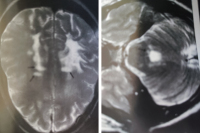

Abbildung 1: MRT: T2-gewichtete Läsionen supratentoriell, infratentoriell und im zervikalen Rückenmark